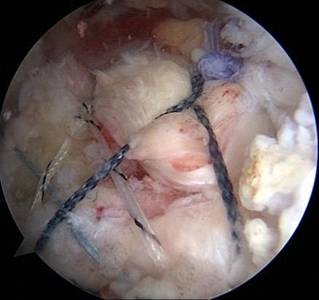

另外,微创成为我院关节科的一大亮点,膝关节周围截骨术,单髁置换术都是微创手术,患者创伤小,恢复快。我院关节科采用直接前路微创髋关节置换术,切口小,只有8-10cm,顺肌间隙进入,不切断任何肌肉,出血少,无痛,关节脱位率低,术后康复快。关节镜下微创肩袖撕裂修补,冻结肩松解,肩关节撞击症肩峰下减压术,膝关节交叉韧带损伤修补等手术,避免大切口、大创伤、恢复快。

全膝关节表面置换术治疗重度骨性关节炎、全髋关节置换术治疗晚期股骨头坏死、先天性髋关节发育不良、股骨颈骨折。微创钻孔减压、腓骨移植、髋关节外科脱位大转子截骨技术治疗股骨头坏死。直接前路微创髋关节置换术。膝关节周围截骨术、单髁置换术阶梯治疗膝关节骨性关节炎。人工反置式肩关节置换术治疗巨大肩袖损伤;关节镜下微创肩袖撕裂修补术,肩峰下减压术及肩关节脱位的手术。髋膝关节置换术后翻修术。

关节镜下肩袖损伤修复术治疗肩袖损伤

优点:损伤小、恢复快。